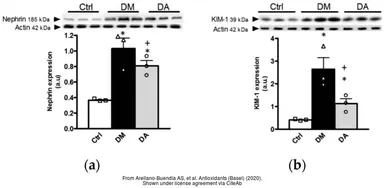

The data was published in the 2020 in Antioxidants (Basel). PMID: 33203103

The data was published in the 2020 in Antioxidants (Basel). PMID: 33203103